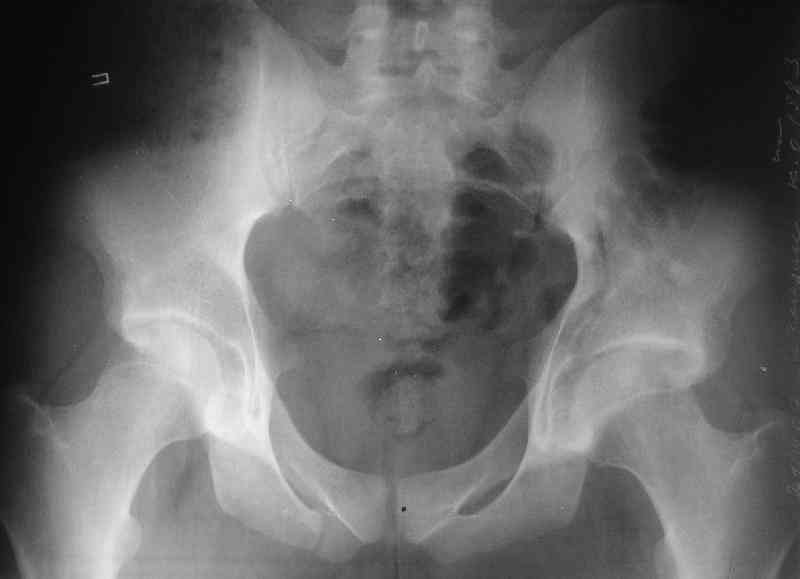

What is your indication for surgical management? What kind of fracture do you think it is? It looks like a transverse type although it has been a couple of years since I looked at an acetabular fracture.

The last two images from the 3-D CT scan certainly makes the fracture look worse than the plan radiographs.

The joint is non-concentric as the head appears to be either "following the caudal segment", or the dome component is displaced from the tethered head... or so it seems... and he's young... so, many fracture surgeons would recommend reduction and fixation.

Some more images. Does it help to guess which part of the acetabulum is displaced?

Normal appearing SI joints and a healed posterior column limb... my bet's on caudal segment displacement.

The anterior element of the fracture is so low and the anterior roof arc angle must be at least 60 deg.